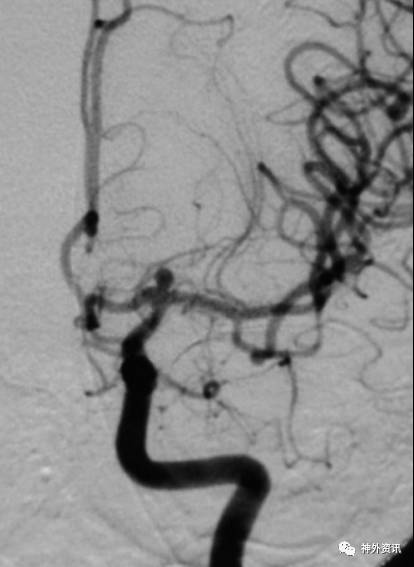

单弯塑形

动脉瘤指向与载瘤动脉走向弧度一致(通常A1和M1弓背向上)

(1)指向下方的前交通动脉瘤

(2)指向下方的大脑中动脉分叉动脉瘤

(3)动脉瘤指向与载瘤动脉走向弧度一致的远端动脉瘤

病例一